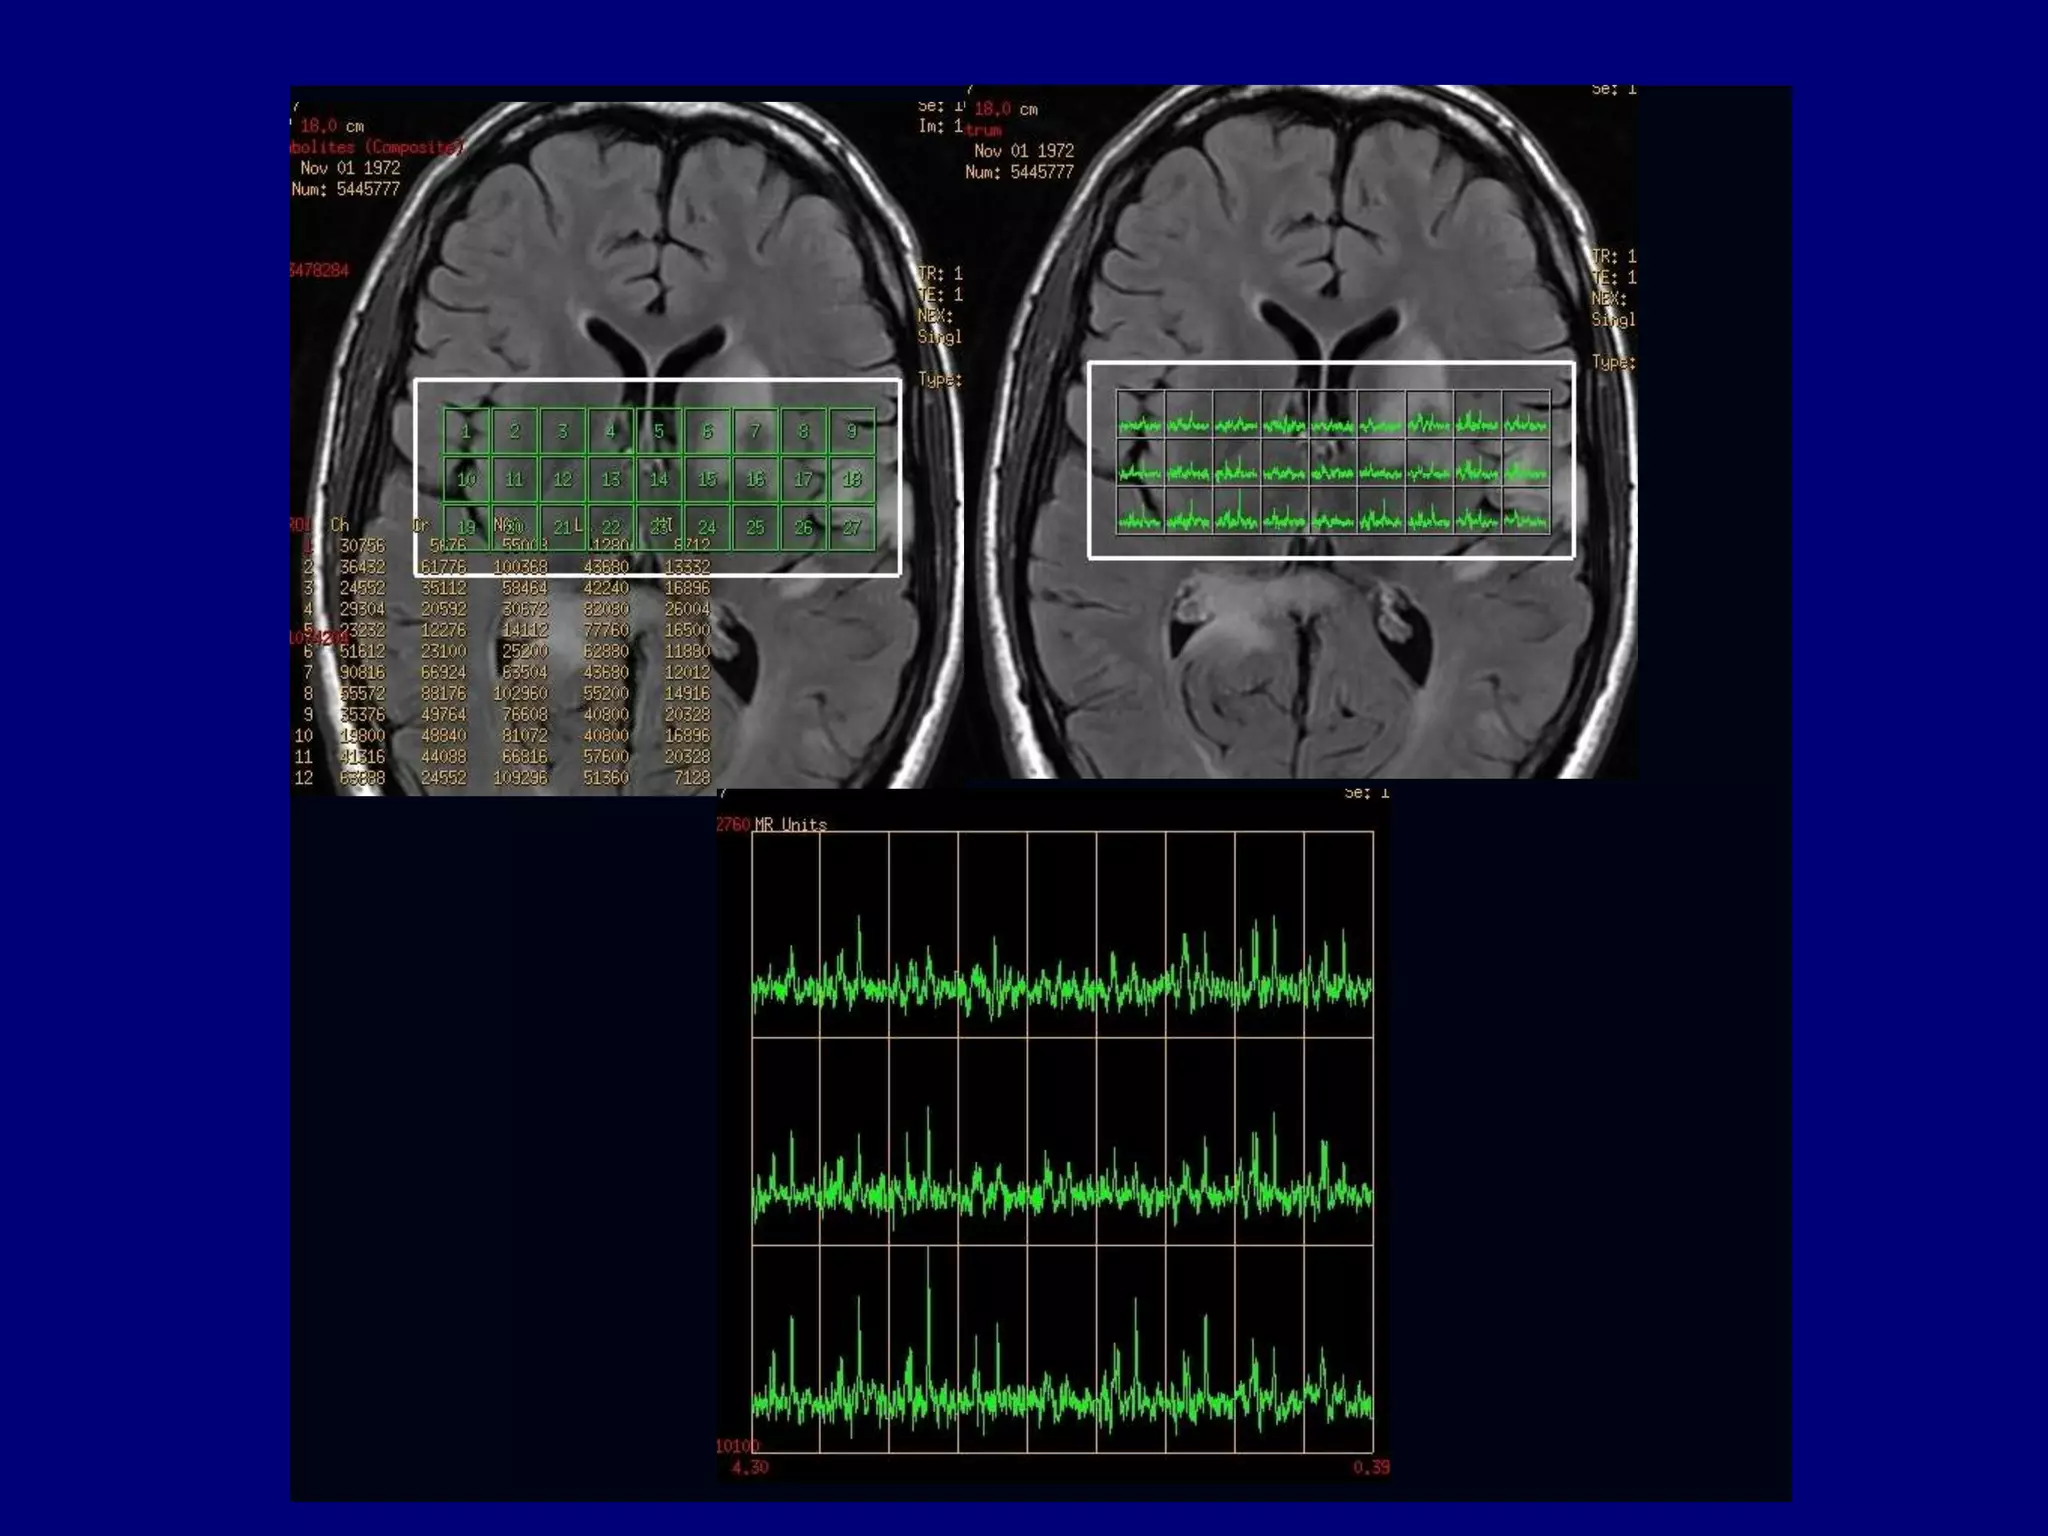

NAA

Choline

2D- CSI (PROBE: TE=144, Section=10mm, NEX=1

Creatine

ROI 2

ROI 3

ROI 4

ROI 5

ROI 8

ROI 12

ROI 13

ROI 14

ROI 7

ROI 9

ROI 15

MR Spectroscopy

Large Choline peak

 High choline/creatine ratio

 Lactate peak may be seen